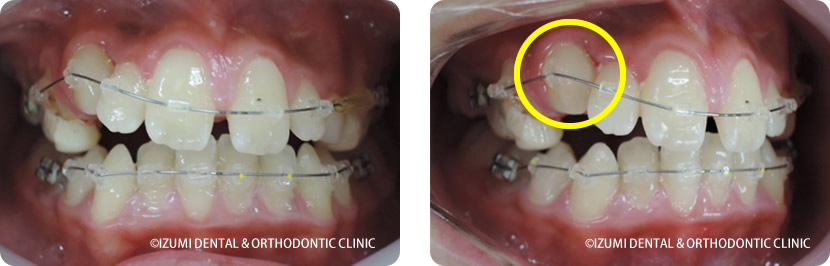

①乳臼歯にレジンを盛る事で第一大臼歯の咬み合わせに隙間が出来ました。

咬合の高さをレジンによって高くすることで、第一大臼歯(6歳臼歯)が正常なところまで萌出できる隙間が確保されました。

②約2か月で隙間が埋まり第一大臼歯が咬み合いました。